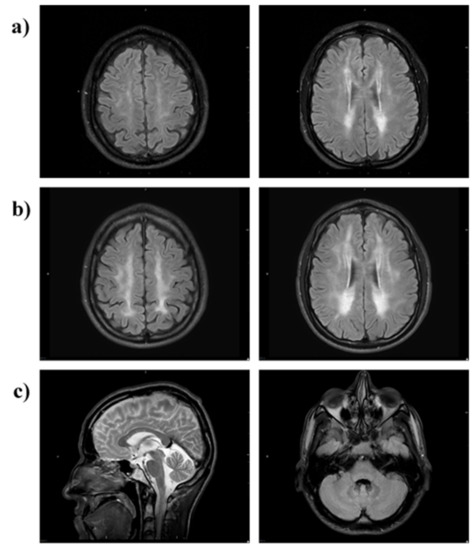

- Scarpelli, M.; Ricciardi, G.K.; Beltramello, A.; Zocca, I.; Calabria, F.; Russignan, A.; Zappini, F.; Cotelli, M.S.; Padovani, A.; Tomelleri, G.; et al. The Role of Brain MRI in Mitochondrial Neurogastrointestinal Encephalomyopathy. Neuroradiol. J. 2013, 26, 520–530. [Google Scholar] [CrossRef] [PubMed]

- Gramegna, L.L.; Pisano, A.; Testa, C.; Manners, D.N.; D’Angelo, R.; Boschetti, E.; Giancola, F.; Pironi, L.; Caporali, L.; Capristo, M.; et al. Cerebral Mitochondrial Microangiopathy Leads to Leukoencephalopathy in Mitochondrial Neurogastrointestinal Encephalopathy. Am. J. Neuroradiol. 2018, 39, 427–434. [Google Scholar] [CrossRef]